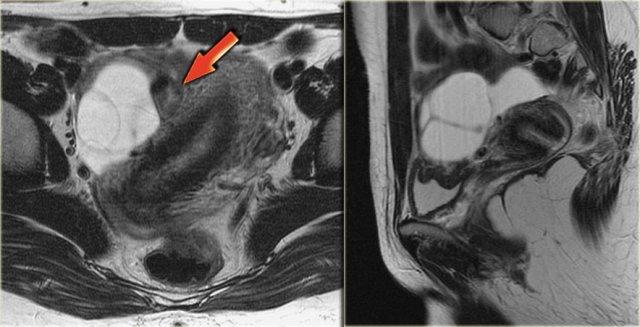

Hình ảnh chuỗi xung T2W mặt cắt ngang và mặt cắt đứng dọc của cùng một bệnh nhân.

Buồng trứng phải chứa nhiều nang đơn giản tăng tín hiệu T2 với bờ mỏng và không có thành phần đặc.

Trên hình mặt cắt ngang, có một tổn thương giảm tín hiệu T2, tức là nang phức tạp (mũi tên).

Có một lượng nhỏ dịch cổ trướng quanh buồng trứng phải, nhưng không đủ để gợi ý lo ngại về khả năng u tân sinh.

Trên chuỗi xung T1W không có kỹ thuật xóa mỡ, nang phức tạp tăng tín hiệu, gợi ý thành phần mỡ hoặc máu.

Trên chuỗi xung T1W có kỹ thuật xóa mỡ, tổn thương vẫn tăng tín hiệu, loại trừ tổn thương chứa mỡ.

Sau khi tiêm Gd, không có ngấm thuốc, xác nhận đây là nang buồng trứng xuất huyết.

Lạc nội mạc tử cung dạng nang (endometrioma) cần được đưa vào chẩn đoán phân biệt.

Lưu ý rằng hình ảnh trừ (subtraction) là tốt nhất để chứng minh sự vắng mặt của ngấm thuốc trong tổn thương tăng tín hiệu trên chuỗi xung T1W trước tiêm thuốc tương phản từ.